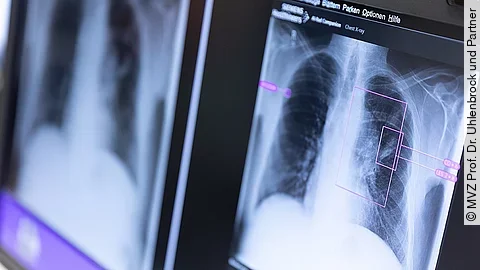

Noch eine Besonderheit für den Einsatz in der Pandemie: Covid-19-Patienten, die sich zur Behandlung ins Krankenhaus begeben, haben in der Regel Atemprobleme und dadurch Mühe, die Luft während des Messvorgangs anzuhalten. Canon Medical verwendet deshalb in den Containern keine älteren Geräte, sondern neueste Highend-CT-Scanner, die für einen Thorax-Scan nur 2 Sekunden benötigen. Diese modernen CT-Scanner haben außerdem den Vorteil, dass sie mit einer niedrigen Strahlendosis bereits eine gute Bildqualität liefern. Bei älteren Geräten gilt die Faustregel: Je höher die Strahlung, desto besser das Bild. Die niedrige Strahlendosis ist auch deshalb sinnvoll, weil es unter den Covid-Patienten im Krankenhaus auch jüngere Patienten gibt. Für die Rekonstruktion werden Hochleistungs-Computer benötigt. Canon Medical Systems zum Beispiel hat hierfür ein neues Verfahren auf der Basis von künstlicher Intelligenz im Einsatz. „Wir erzielen mit unserem Deep-Learning-Algorithmus eine Rauschunterdrückung, mit der trotz der geringen Strahlendosis ein gutes Bild erhalten“, sagt Henneke. Die Rekonstruktion der Schichtbilder findet direkt im Container statt.